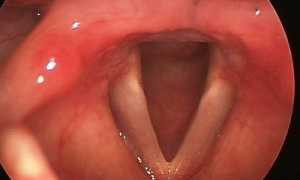

Ксилометазолин является деконгестантом, то есть за счет взаимодействия с альфа-адренорецепторами он сужает просвет сосудов в слизистой носа и глотки, что сокращает отечные явления и убирает покраснение поверхности слизистой оболочки, как следствие — уменьшается количество отделяемого из носовых ходов и облегчается дыхание заложенного носа.